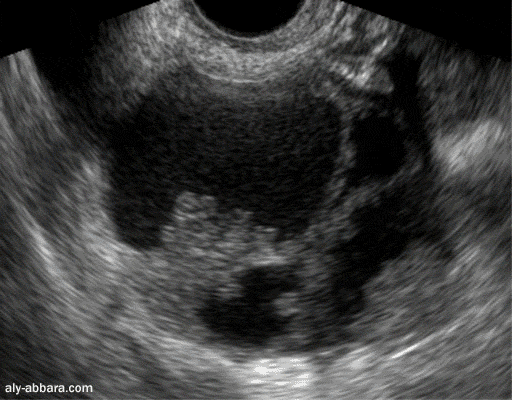

Kyste de l'ovaire droit

Il s'agit d'une tumeur ovarienne multicloisonnée

avec des

végétations

endophytiques (à l'intérieure du kyste) et

exophytiques (à

la surface extérieure de l'ovaire)

(Cystadénocarcinome séreux de haut grade de l'ovaire)